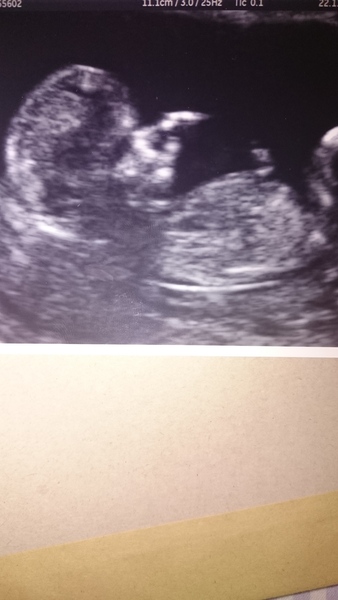

Internet stopped working last night. One very wriggly baby :) measuring bang on for dates so far. Trying to work out if it's a good thing or not that the sonographer remembers me from almost 4 years ago GrinHmm

12+3

purple lovely scan xx